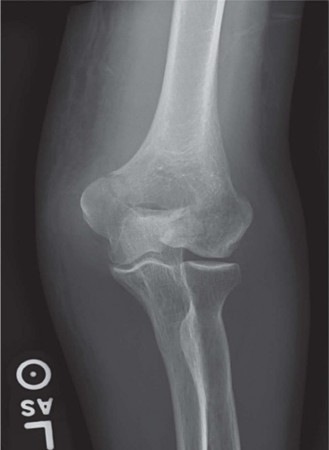

A 36-year-old, right-hand-dominant male presents to the emergency department with right arm and elbow pain af…